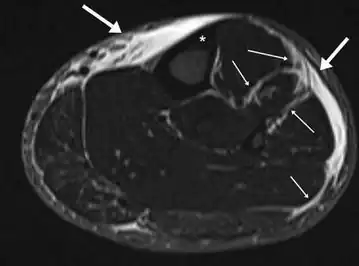

MRI of the left lower leg-severe “shin-splint”

Magnetic resonance image of the lower leg in the coronal plane showing high signal (bright) areas around the tibia as signs of shin splints.

Other potential causes include stress fractures, compartment syndrome, nerve entrapment, and popliteal artery entrapment syndrome.[16] If the cause is unclear, medical imaging such as a bone scan or magnetic resonance imaging (MRI) may be performed.[3] Bone scans and MRI can differentiate between stress fractures and shin splints.[11]